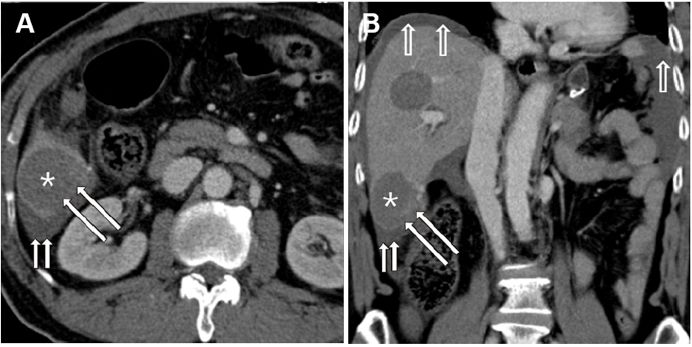

4、胃肠间质瘤导致的胃十二指肠套叠

Gastroduodenal intussusception due to gastro-intestinal stromal tumor

Clin Case Rep.

IF:NA

女性患者,42岁,因“上腹部疼痛伴间歇性呕吐半年”入院治疗。临床主要表现为急性胃流出道梗阻。血化验提示患者有贫血;胃镜提示胃窦幽门区前壁粘膜下肿物,通过幽门进入十二指肠,肿物表面粘膜有溃疡;腹部CT提示肿物8×7×4cm大小,胃窦起源进入十二指肠至水平部,不均一强化。患者接受剖腹探查,胃肿物局部切除术。术后恢复顺利。(手术标本见图)

图示 GIST切除标本 肿块顶点(红色箭头), 肿物基底 (绿色箭头),部分胃壁 (黄色箭头)

浙江大学医院附属邵逸夫医院

上述文章是一篇个案报告,而且不是个很完整的个案报告,因为文中并没有提及该肿块病理检查的结果,只是告知为GIST,没有NIH复发风险评估,也没有后续治疗和随访情况。从这篇短文中我只是见识了一个罕见的由GIST而导致上消化道梗阻的病例,见识了GIST作为一个间叶源性肿瘤在胃十二指肠区域膨胀性生长形成了一个奇怪的形状。另外该病例也使我想起了临床上更多见的一种情况,即胃幽门管的带蒂息肉导致幽门关闭不全而形成了胆汁反流性胃炎,所以提示对于胃的小GIST和微小GIST,如果位于贲门或幽门附近,手术干预可以更加积极一些。